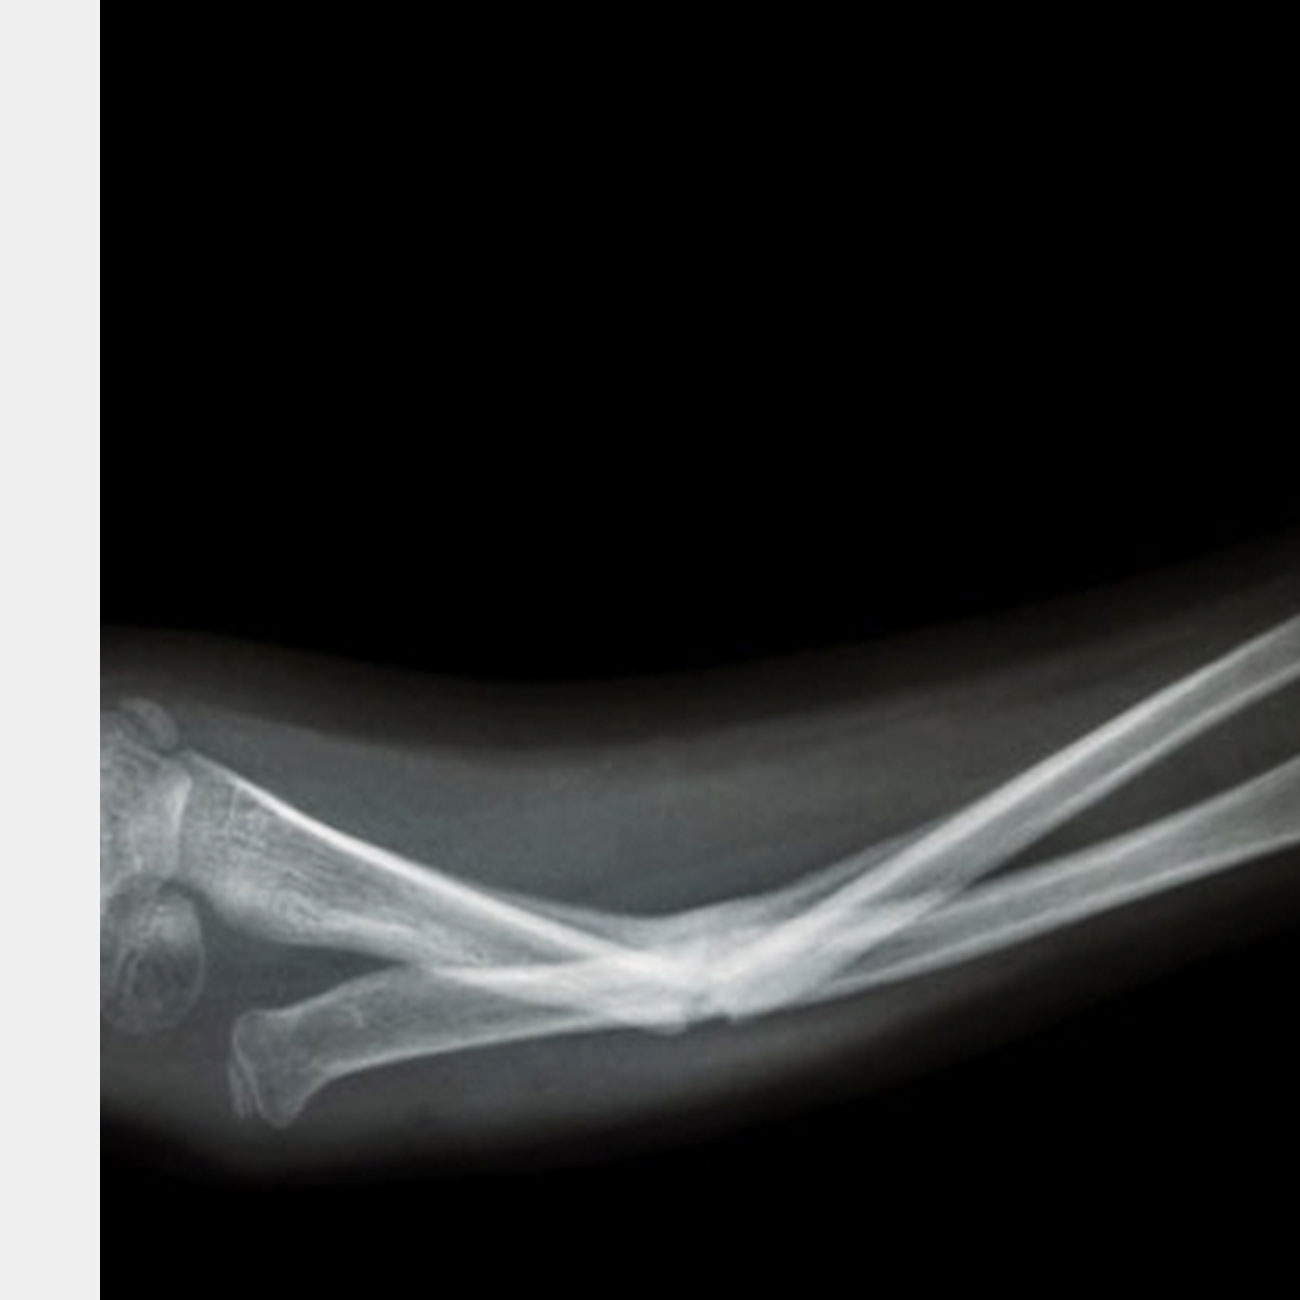

Когда вы были ребенком, вы когда-нибудь подписывались за одноклассника, если тот сломал руку или ногу? Носили за ним портфель? Сломанные кости для ребенка — очень плохо: несколько катастрофических секунд, за которыми следуют месяцы скучного отдыха и восстановления. Но у детей в будущем может быть другая история, поскольку новые технологии позволят нам пересмотреть, как мы восстанавливаем сломанные кости.ve a specific genetic feature (biomarker).

Углеродные наноматериалы могут обладать способностью залечивать кости быстрее, чем Гарри Поттер с заклинанием «костиум залечиум». Исследователи из команда Стефани Сидлик из Университета Карнеги-Меллона протестировали новый состав графена, который биоразлагаемый, имитирует кость, привлекает стволовые клетки и, в конечном итоге, улучшат процесс восстановления скелетов у животных.